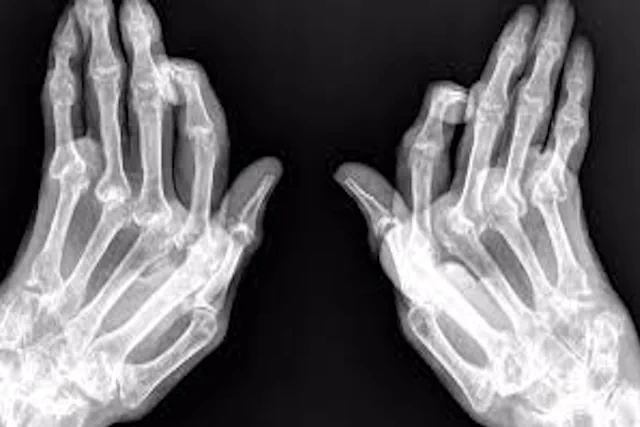

La osteoporosis es una enfermedad ósea progresiva que reduce la densidad y calidad de los huesos, aumentando significativamente el riesgo de fracturas. Aunque existen tratamientos médicos convencionales, los suplementos de Nature’s Bounty representan una alternativa natural y efectiva para fortalecer los huesos y prevenir la pérdida ósea. Estos suplementos están formulados con nutrientes esenciales como calcio, vitamina D3, magnesio, colágeno y zinc, que contribuyen a la salud ósea y muscular, promoviendo una mejor absorción de minerales esenciales.

Consecuencias de Tener Osteoporosis y No Tratarla

La osteoporosis es una enfermedad silenciosa, ya que no presenta síntomas evidentes hasta que ocurre una fractura. No tratar esta condición puede derivar en graves consecuencias para la salud y la calidad de vida. A continuación, te explicamos los efectos negativos de la osteoporosis no tratada y cómo puedes prevenirlos.

- Fracturas Frecuentes: Especialmente en caderas, muñecas y columna vertebral, lo que puede causar dolor severo e incapacidad permanente.